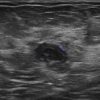

Ung thư vú

» Thông tin: Nữ giới – 50 tuổi.

» Lâm sàng: Kiểm tra sức khỏe.